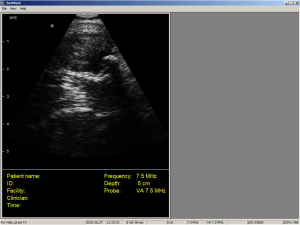

3.This patient was seen by myself at a home visit. I was called out during a remote clinic with the complaint that the patient could not walk. The volunteer ambulance driver and I drove to his house where I found him lying on the couch with a sore calf. He told me he had been running around with his kids 2 days ago , felt a sudden pain in his lower calf, then swelling and ongoing pain there since.

I got an USS image of his lower calf here

How did this USS image aid my clinical management?

3) calf haematoma (not a DVT no need to Ix further)

My feedback : 50% correct. You have not described how your USS interpretation has aided the prehospital clinical management in any of the cases. Case 3 is more than a haematoma.

Remember case 1 is already ventilated so something else you can do and rescan to assess effect. Case 2 excellent. Case 3 you need to more scanning or do a sports medicine term…its the Olympics month remember!

still lost on 3) so I’ll leave it to the experts. Not enough scanning for me yet. Calf tears are a bit beyond me in USS.